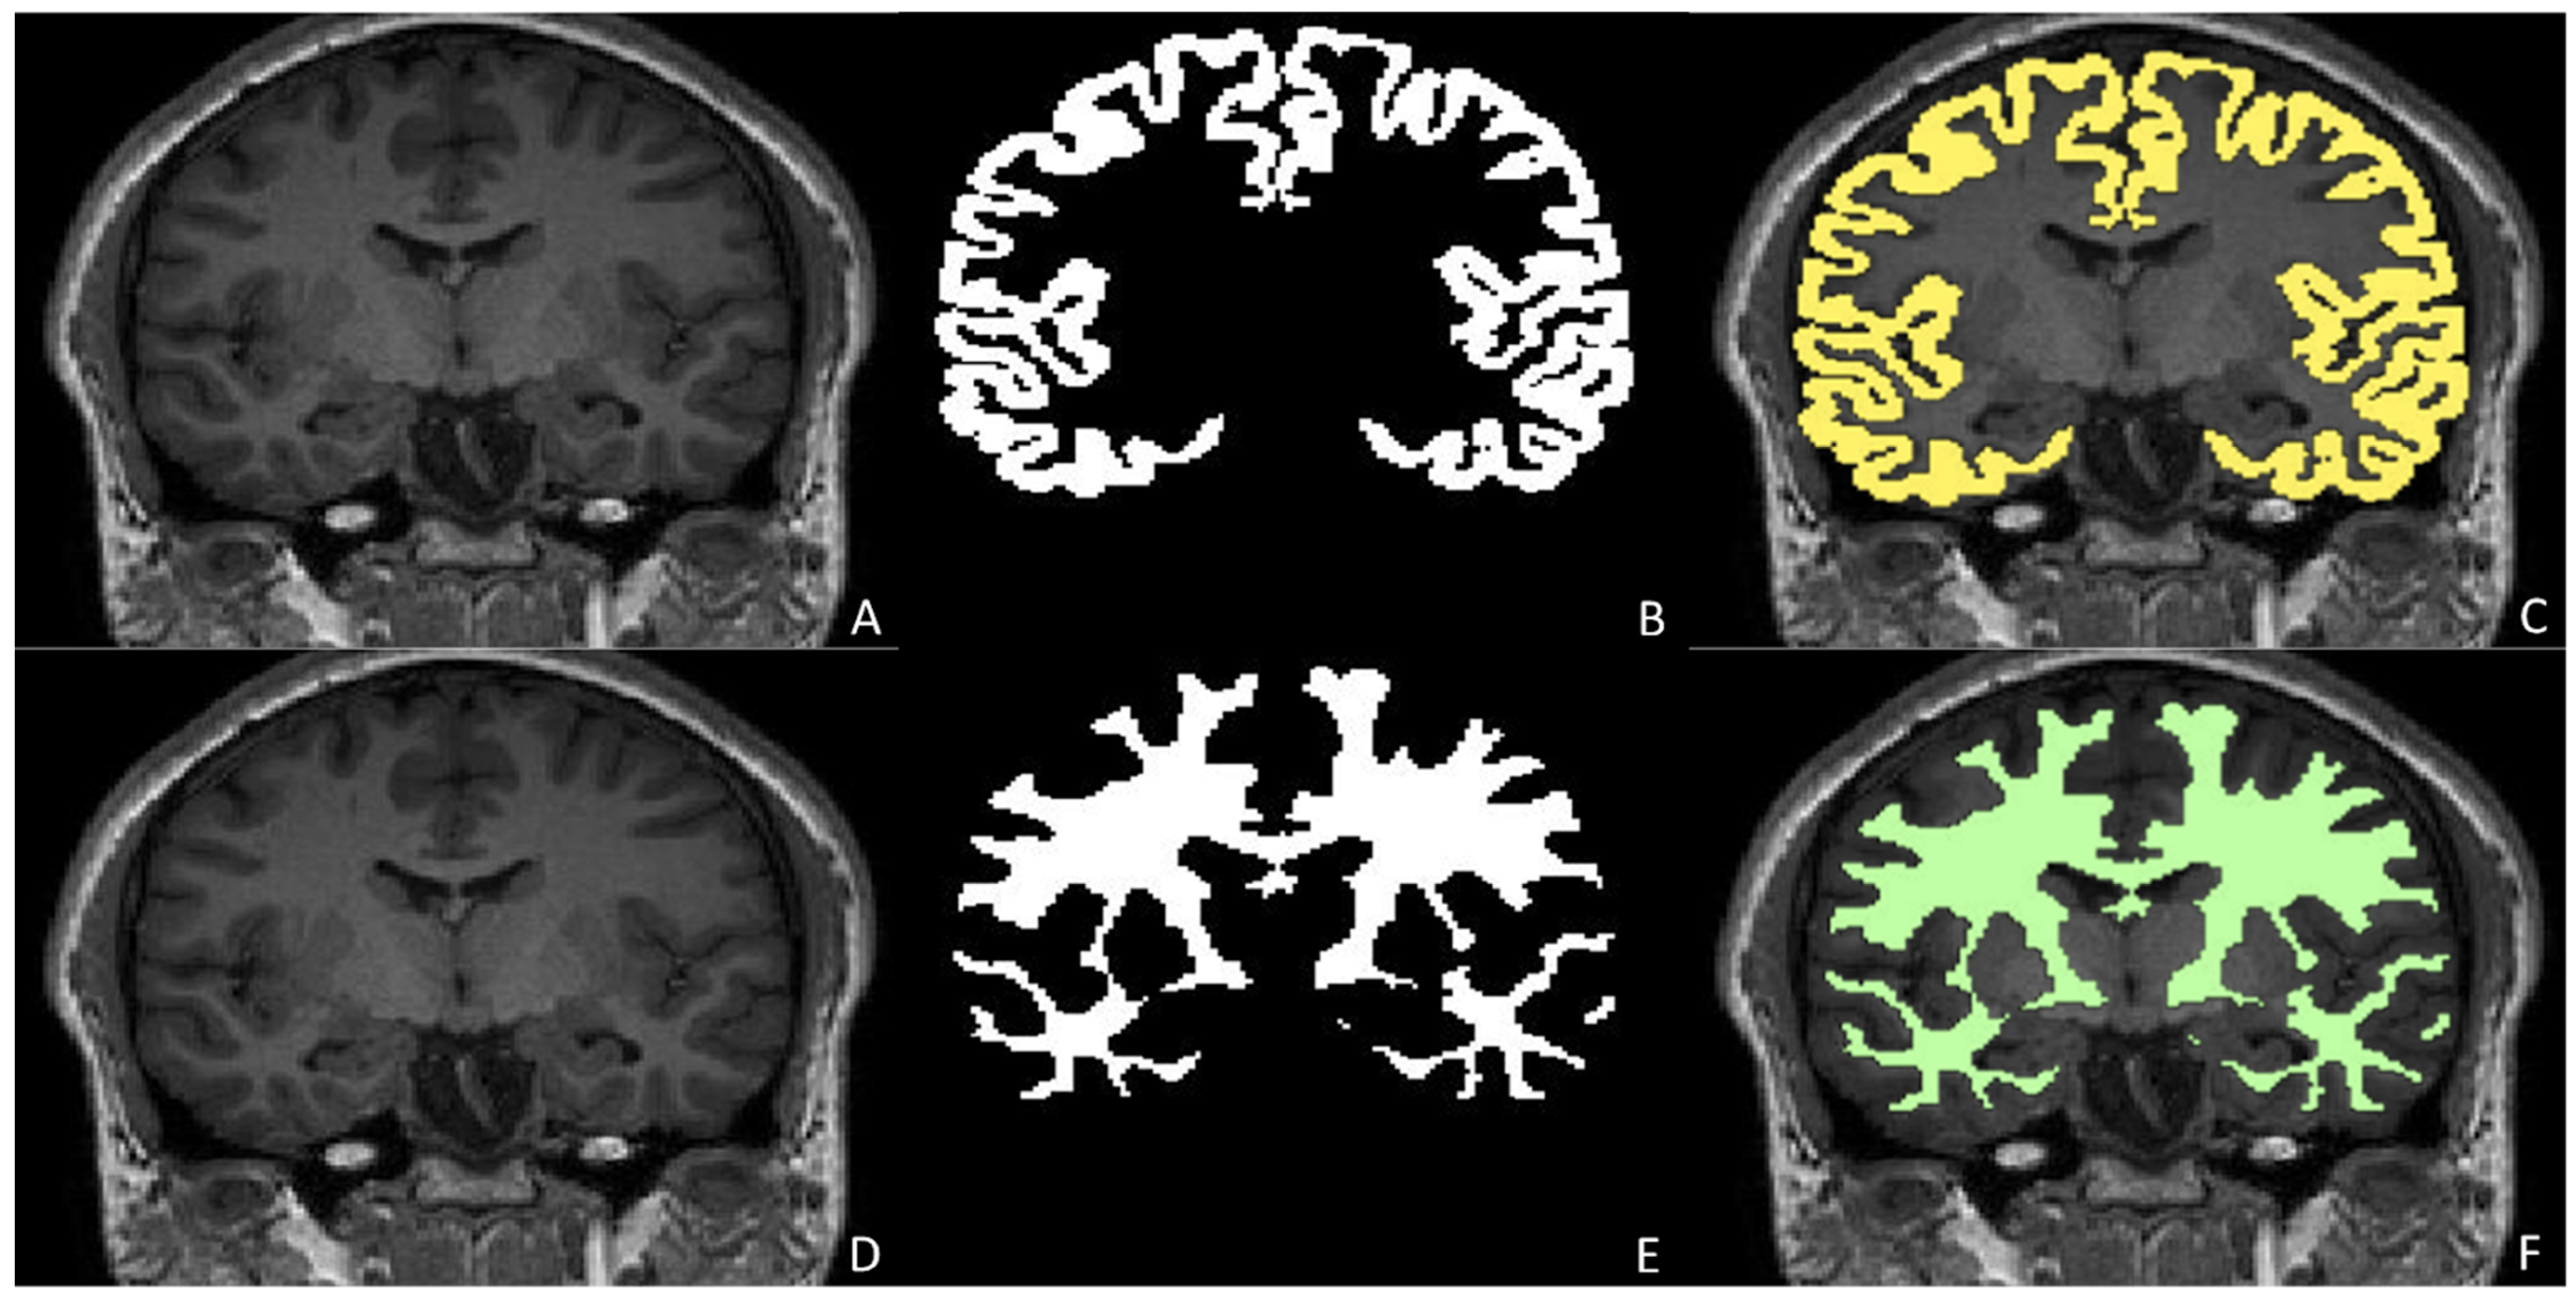

- Grimm, F.; Edl, F.; Kerscher, S.R.; Nieselt, K.; Gugel, I.; Schuhmann, M.U. Semantic Segmentation of Cerebrospinal Fluid and Brain Volume with a Convolutional Neural Network in Pediatric Hydrocephalus-Transfer Learning from Existing Algorithms. Acta Neurochir. 2020, 162, 2463–2474. [Google Scholar] [CrossRef]

- Billot, B.; Greve, D.N.; Puonti, O.; Thielscher, A.; Van Leemput, K.; Fischl, B.; Dalca, A.V.; Iglesias, J.E. SynthSeg: Segmentation of Brain MRI Scans of Any Contrast and Resolution without Retraining. arXiv 2021, arXiv:2107.09559. [Google Scholar] [CrossRef]